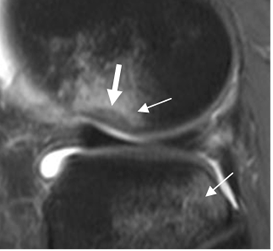

Fig 95 A. Ruptura aguda del LCA.

RM sagital en STIR. Clásica contusión del platillo tibial y el cóndilo femoral lateral, con depresión mayor de 1.5 mm (Flecha gruesa), constituyendo el signo de la muesca.